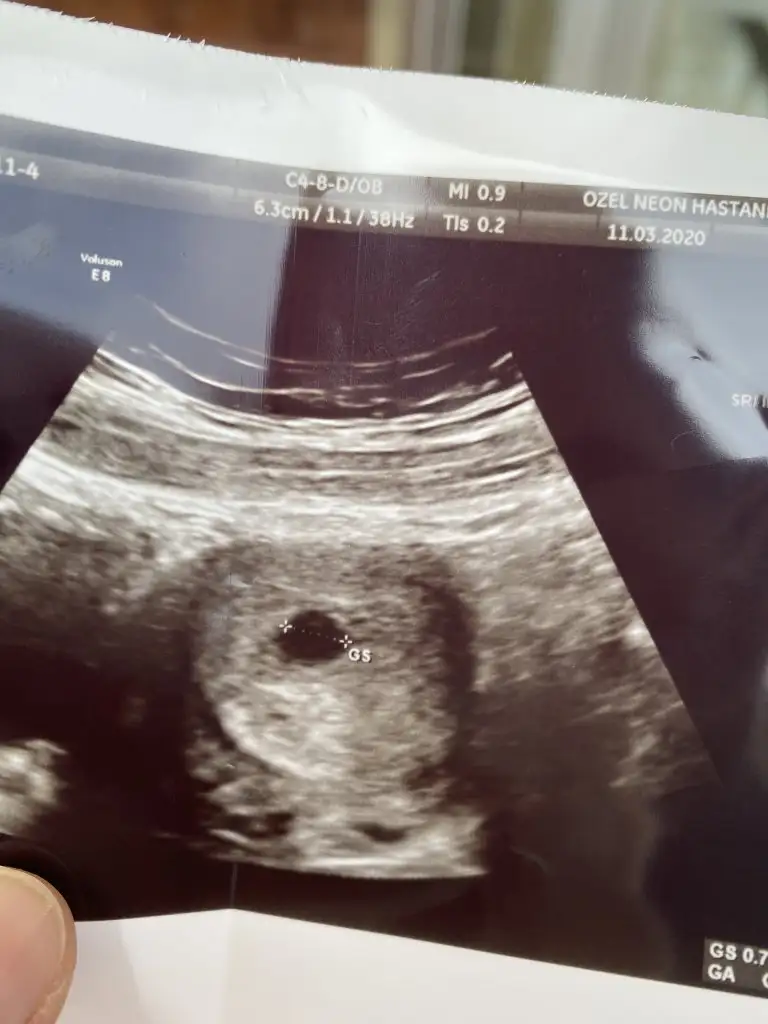

Kızlarrrr bugün kese için randevu vermişti doktor. 5+4üm gittim kese oluşmuş gördük çok şükür. 2 hafta sonra kalp atışı için çağırdı😊😊 beta tekrar bakmadı gerek yok dedi

Eklentiler

• 58AA8540-995E-4AB0-96C2-0E47CA9481E6.webp

58AA8540-995E-4AB0-96C2-0E47CA9481E6.webp

27,3 KB · Görüntüleme: 50

içinde bişey var gibi ama gölgemi acba bebek olsaydı dr derdi dimi :) darısı başımıza

Evet var gibi ama belli etmiyor miniğim kendini😊😊 dpktor dedi boş gibi durmuyor ama bakalım. Rabbim isteyen herkese nasip etsin inşallah. Benim ilk. Geçen ayda kimyasal yaşadım.